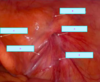

What is this image depicted of the female reproductive tract [1]

Endometriosis